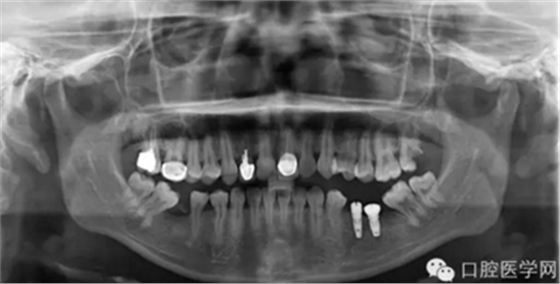

那么今天我给大家展示临床上比较常见的几种品牌的种植体的X光片,网友们可以通过X光片来仔细查看不同种植体之间的区别。因为本人能力有限,不能每一样种植体都拿来尝试使用,所以我目前收集到的种植体的X光片数量有限,但是本人日后还会不断的去寻找不同品牌种植的资料,然后补充道这篇文章中,以供大家参考。

需要特殊声明的是:以下所有的照片中有本人自己的病例术后X光片,也有本人在网络上搜集到的X光片(并非本人的临床病例),所以在此暂不讨论种植体手术植入的角度和设计方案等问题,本文的主要目的是像广大读者展示不同品牌种植体在植入颌骨内拍摄X光片后所显示的形状,用以区别不同品牌的种植体。

第二种种植体是 NobelReplace系统

X光片显示为: